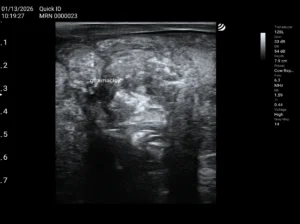

4. USG płuc – narzędzie terenowe, szybkie i skuteczne:

• ocena obecności linii A, B, C

• konsolidacje, ropnie, płyn w jamie opłucnej

• monitorowanie leczenia

W BRD ultrasonografia to szybkie i skuteczne narzędzie, które warto wdrożyć w każdej praktyce terenowej. Daje jasny obraz sytuacji w płucach – pozwala działać szybciej, celniej i skuteczniej. Im wcześniej rozpoznamy BRD, tym większe szanse na pełne wyleczenie!